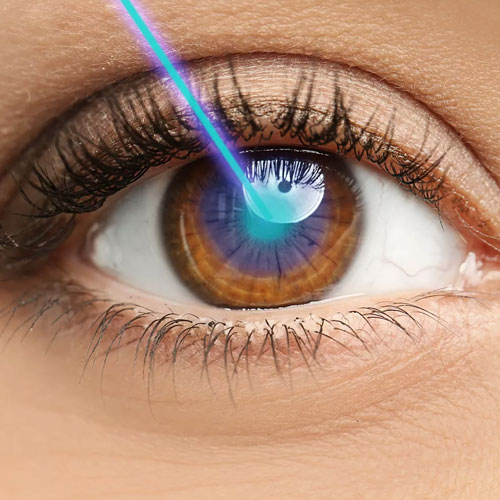

Dr. Abdul Rasheed, one of the leading Ophthalmologist and Cataract & Refractive surgeon in the city of Hyderabad provides extensive and comprehensive care for all your eye sight issues. Vision disturbance are one of the few issues which have the capacity to completely disturb our daily life and activities. Correcting them in the right way to avoid further complications or risk is the motto of Dr. Abdul Rasheed. With age comes cataract, Dr.Rasheed is an expert in complicated cataracts such as small pupil, zonular dialysis, mature / Brunescent cataracts, corneal scars, shallow Ac, etc., as well as complicated refractive surgery cases like RK scars, corneal scars, etc. While coming to refractive surgeries, Dr. Abdul Rasheed strongly believes and says "Any patient irrespective of complexity, who can be refracted to 6/6 can be treated to read the same without glasses." He has treated many patients of keratoconus who had extreme distortion of vision. After INTACS implantation followed by ICL, patients were able to regain normal vision.